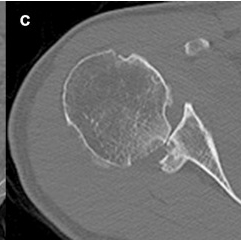

CT

Hill Sachs lesion / posterior bony bankart / glenoid retroversion

Critical posterior glenoid bone loss

- compared successful posterior labral surgery with unsuccessful

- 11% glenoid bone loss - 10 x failure rate

- 15% glenoid bone loss - 25 x failure rate

Glenoid Osteotomy

Indication

Posterior instability with retroversion > 10 degrees / glenoid dysplasia

- osteotomy parallel to articular surface, 1.5 cm from articular surface

- preserves anterior 1 cm of glenoid to prevent iatrogenic fractures